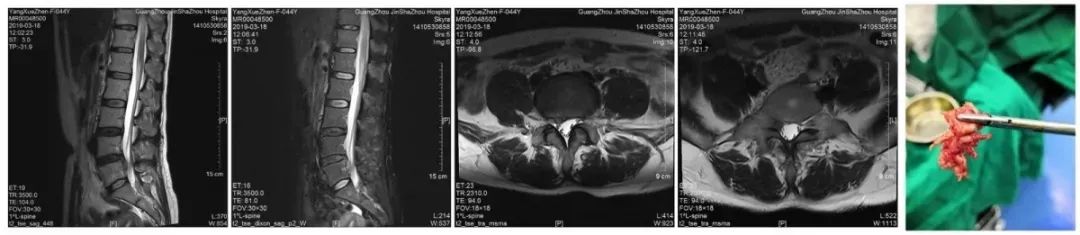

研究中对临床治愈的病人,做脊椎X线、CT、MRI复查,可见椎体和关节的排列、椎管矢状径、椎间孔变窄已恢复到代偿范围或正常范围,而椎间盘膨出、突出、韧带钙化和骨质增生基本上与发病期无明显改变,这证明疗效主要来源于恢复椎管、椎间孔的正常位置和代偿空间。

而对于脊椎椎管、椎间孔位置不正确,失去了代偿空间,脊髓及神经根无可逃逸的空间,仍采用保守治疗,效果欠佳,治疗是徒劳的!

而需要借助外科手术,才能解决椎间盘突出物与脊髓、神经的空间位置问题才能根本上解决问题。至于选择哪一种治疗方式,会有什么样的治疗效果,当然要咨询临床经验丰富的专科医师,获取良好治疗效果。